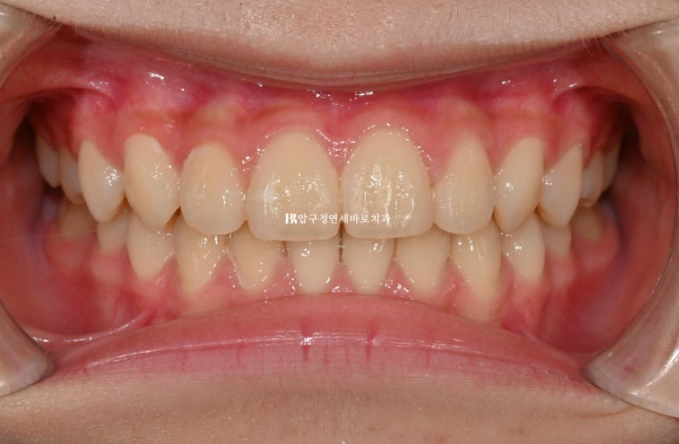

24.09

중심선은 정확히 맞고

어금니 교합은 1급 교합관계를 보입니다.

배열도 좋습니다.

그 사이 마지막으로 맹출하는 두번째 큰어금니까지 잘 나오고 있습니다.

소아교정장치로 시작했지만 성인때 교정을 다시 할 필요가 없을 정도로 모든 게 좋습니다.